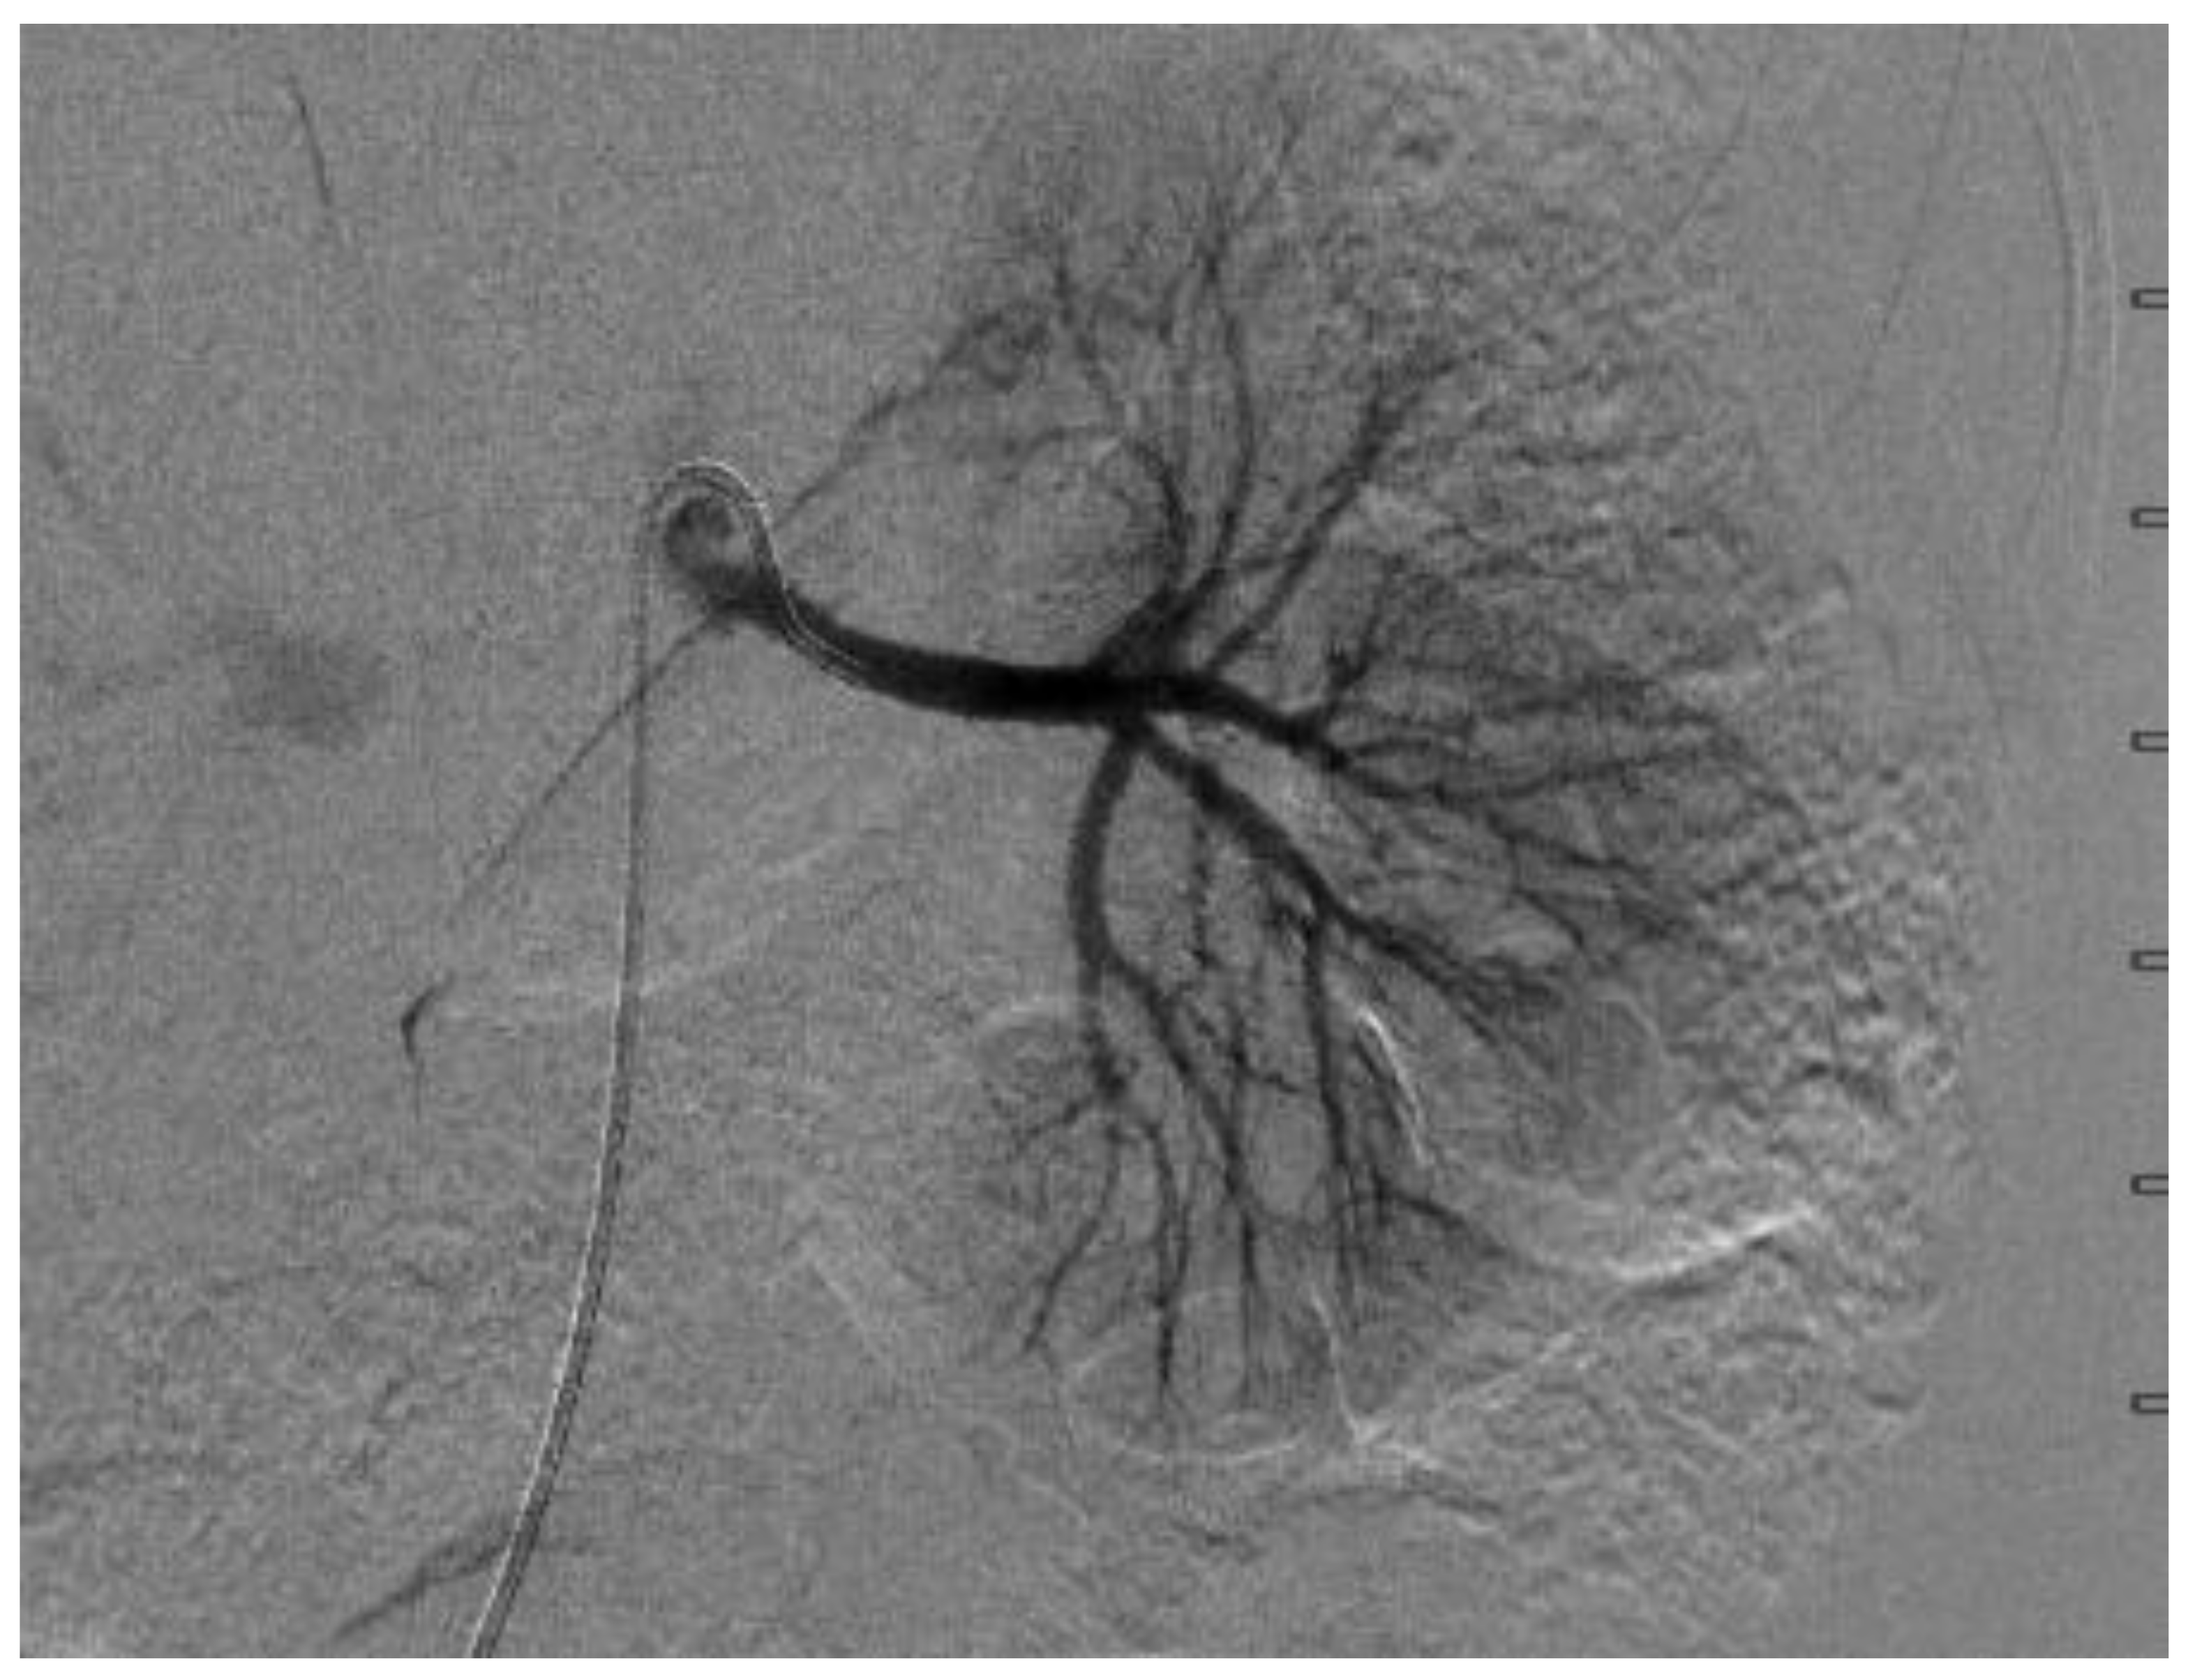

A few days later, she underwent a digital subtraction angiogram (DSA), which showed a beaded appearance of the right proximal main RA, which caused a focal stenosis with post-stenotic dilatation (Figure 3 and Figure 4). The pressure gradient across the stenotic lesion was 40 mm Hg. There was normal renal parenchymal perfusion. The left RA demonstrated a normal appearance of the main and branch arteries with normal renal parenchymal perfusion and no evidence of stenosis and irregularity. A diagnosis of right RA stenosis, most likely due to focal FMD, was made. In conjunction with vascular surgery and intervention radiology, it was collectively decided not to pursue the intervention of the stenotic lesion due to the risk of complication, specifically the injury or dissection of the right RA, especially because her BPs were relatively controlled on five antihypertensive agents. Subsequent to the angiogram, enalapril was added once bilateral RA stenosis was excluded for optimal BP control. A CTA of the head and neck vessels to look for evidence of FMD in the head and neck showed a normal vasculature of the vessels. Baby aspirin was started to prevent thromboembolic events.

Figure 4.

Digital subtraction angiography of the left renal artery, which showed no stenosis.